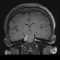

Εικόνα 2: Αριστερά, φυσιολογική μαγνητική τομογραφία (a-c) όπου φαίνεται ότι δεν υπάρχει πίεση επί του νωτιαίου μυελού και τα νευρικά δεμάτια (έγχρωμη εικόνα) δεν είναι συμπιεσμένα. Δεξιά, αυχενική μοίρα με εικόνα σπονδύλωσης και πίεση του νωτιαίου μυελού.